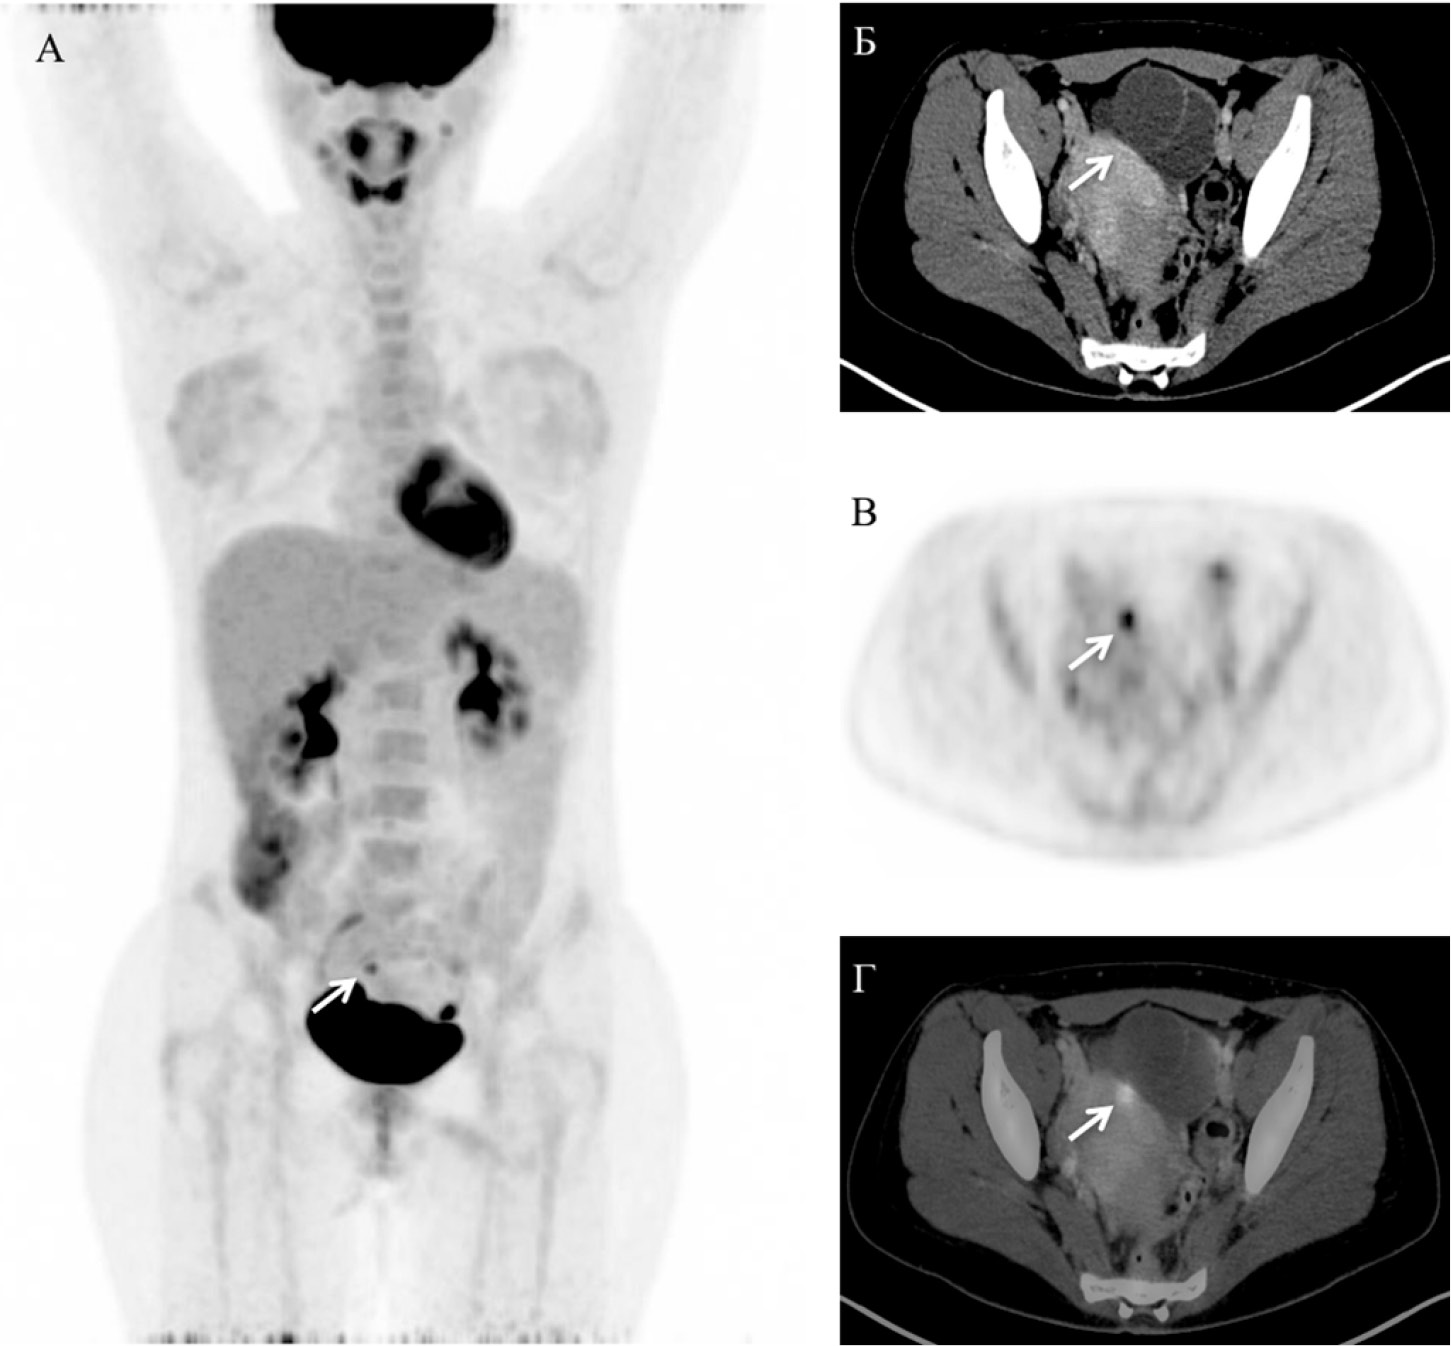

Спустя полтора года после окончания лечения (2016 г.) у пациентки зафиксировано динамическое увеличение уровня β-ХГЧ с 46 до 187 мМЕ/мл. При обследовании в «НМИЦ онкологии им. Н.Н. Блохина» (экспертное УЗИ брюшной полости и малого таза, забрюшинного пространства, КТ органов грудной полости) опухоли не обнаружено. Для уточнения локализации рецидивной опухоли выполнена ПЭТ/КТ с 18F-ФДГ в режиме от основания черепа до середины бедра, при которой определялось повышенное накопление РФП до макс SUV 3,77 в гиподенсном узловом образовании в серозной оболочке передней стенки верхней трети тела матки, размерами до 0,5 см в диаметре (рис. 1). Принято решение о выполнении органосохраняющей операции – гистеротомии, туморэктомии. Накануне операции больной повторно выполнено УЗИ малого таза и в серо-шкальном режиме визуализировалось опухолевое образование 0,7 см в диаметре.

Рис. 1. Позитронная эмиссионная томография (MIP-реконструкция) во фронтальной проекции (А), компьютерная томография с внутривенным контрастным усилением (Б), позитронная эмиссионная томография (В), совмещённое ПЭТ/КТ-изображение (Г) в аксиальной проекции. Стрелками указано очаговое патологическое накопление 18F-ФДГ (А, В, Г) в узловом образовании серозной оболочки верхней трети тела матки (Б)

Пациентке выполнена органосохраняющая гистеротомия, иссечена опухоль диаметром 0,7 см в пределах здоровых тканей. Послеоперационный период протекал без осложнений. В дальнейшем отмечалось снижение уровня β-ХГЧ и его нормализация через 3 нед. По результатам гистологического исследования – эпителиоидная трофобластическая опухоль. Дополнительного лечения не проводилось. Время наблюдения – 3,5 г.